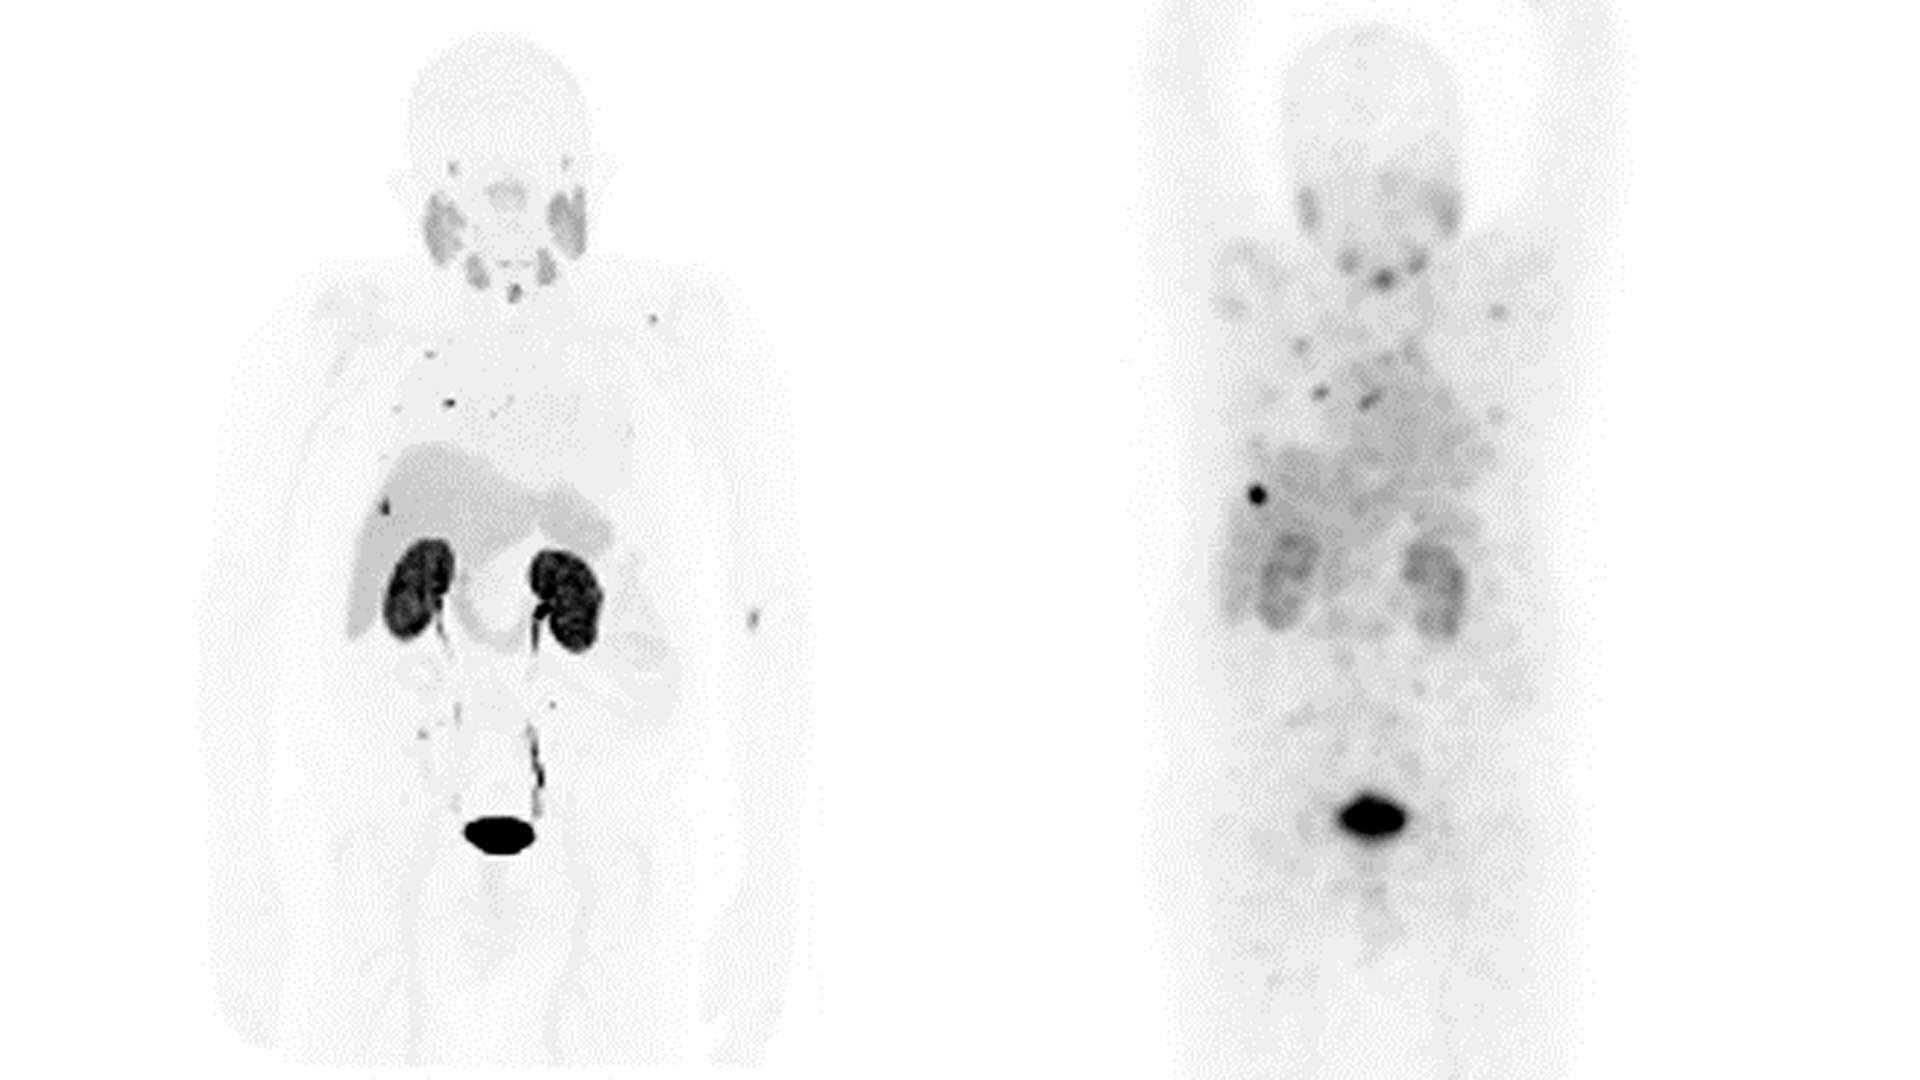

La dosimetría precisa ayuda a evaluar y controlar la dosis absorbida por órganos sensibles y lesiones. El proceso de dosimetría puede ser complicado, ya que requiere el procesamiento de varios estudios, incluida la segmentación de órganos y lesiones, además del uso de métodos complejos y tediosos para evaluar la dosis.

Diseñada para una dosimetría y cuantificación eficientes, Q.Thera AI es la solución de GE HealthCare para la monitorización de tratamientos teragnósticos potenciada por IA. Q.Thera AI segmenta los volúmenes de las lesiones y los órganos del paciente automáticamente, mediante el uso de IA. También cuantifica y calcula de manera automática el porcentaje de dosis inyectada, así como la dosis absorbida por órgano y lesión.

Este flujo de trabajo está diseñado para posibilitar una reducción del tiempo6 desde la carga de datos hasta el cálculo de la dosis, además del número de clics necesarios para lograrlo, a fin de mejorar el flujo de trabajo.

Q.Volumetrix AI

La solución integral de GE HealthCare para la segmentación y cuantificación avanzadas se potencia con IA. Ofrece capacidades avanzadas de segmentación y de cuantificación para datos de SPECT/TC y TEP/TC sin obstaculizar el flujo de trabajo para estudios basales y longitudinales. Proporciona una reconstrucción eficaz con compensación de la atenuación, la dispersión y la resolución. Además, constituye un método sencillo y automático para la segmentación de hígado, riñón, huesos, pulmón, tejido superficial, así como las lesiones. Todo ello es importante para la evaluación y la monitorización del tratamiento teragnóstico. La monitorización cuantitativa permite evaluar la dosis absorbida en los tumores, lo que ayuda a evaluar la respuesta personalizada. También proporciona información sobre la reducción de la carga tumoral en cada ciclo.